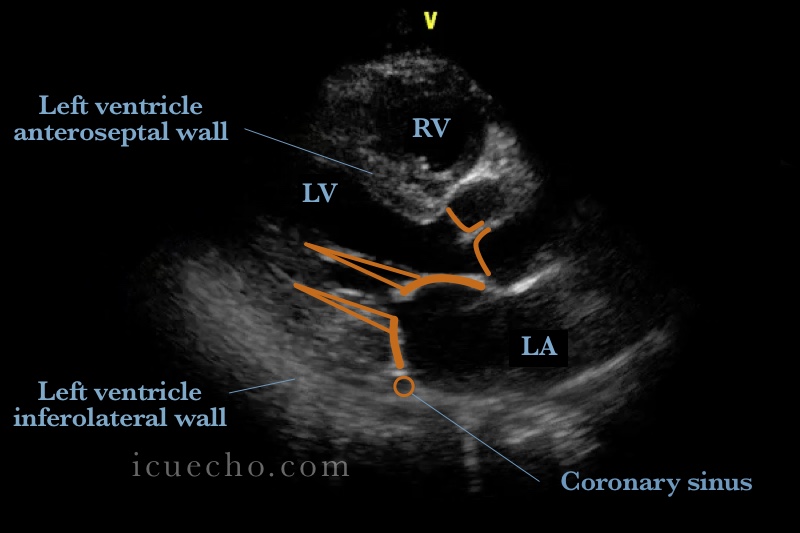

From www.icuecho.com

Parasternal long axis ICU & Echo Long Axis Ultrasound Definition The plax view is traditionally the first view of a standard transthoracic echocardiographic examination. All imaging modalities define, orient and display the heart using the long axis of the left ventricle and selected planes oriented at 90° angles relative to the long axis. The parasternal long axis view is often abbreviated as psla or plax. The short axis (sa) approach. Long Axis Ultrasound Definition.